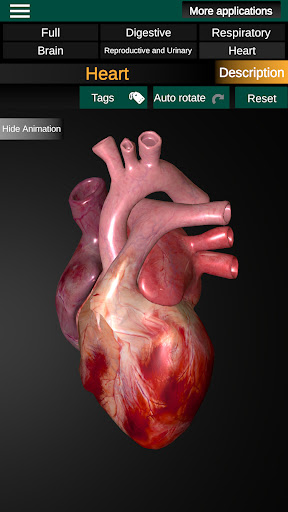

* Jantung, yang meliputi atrium, ventrikel, aorta, dan animasi organ ini.